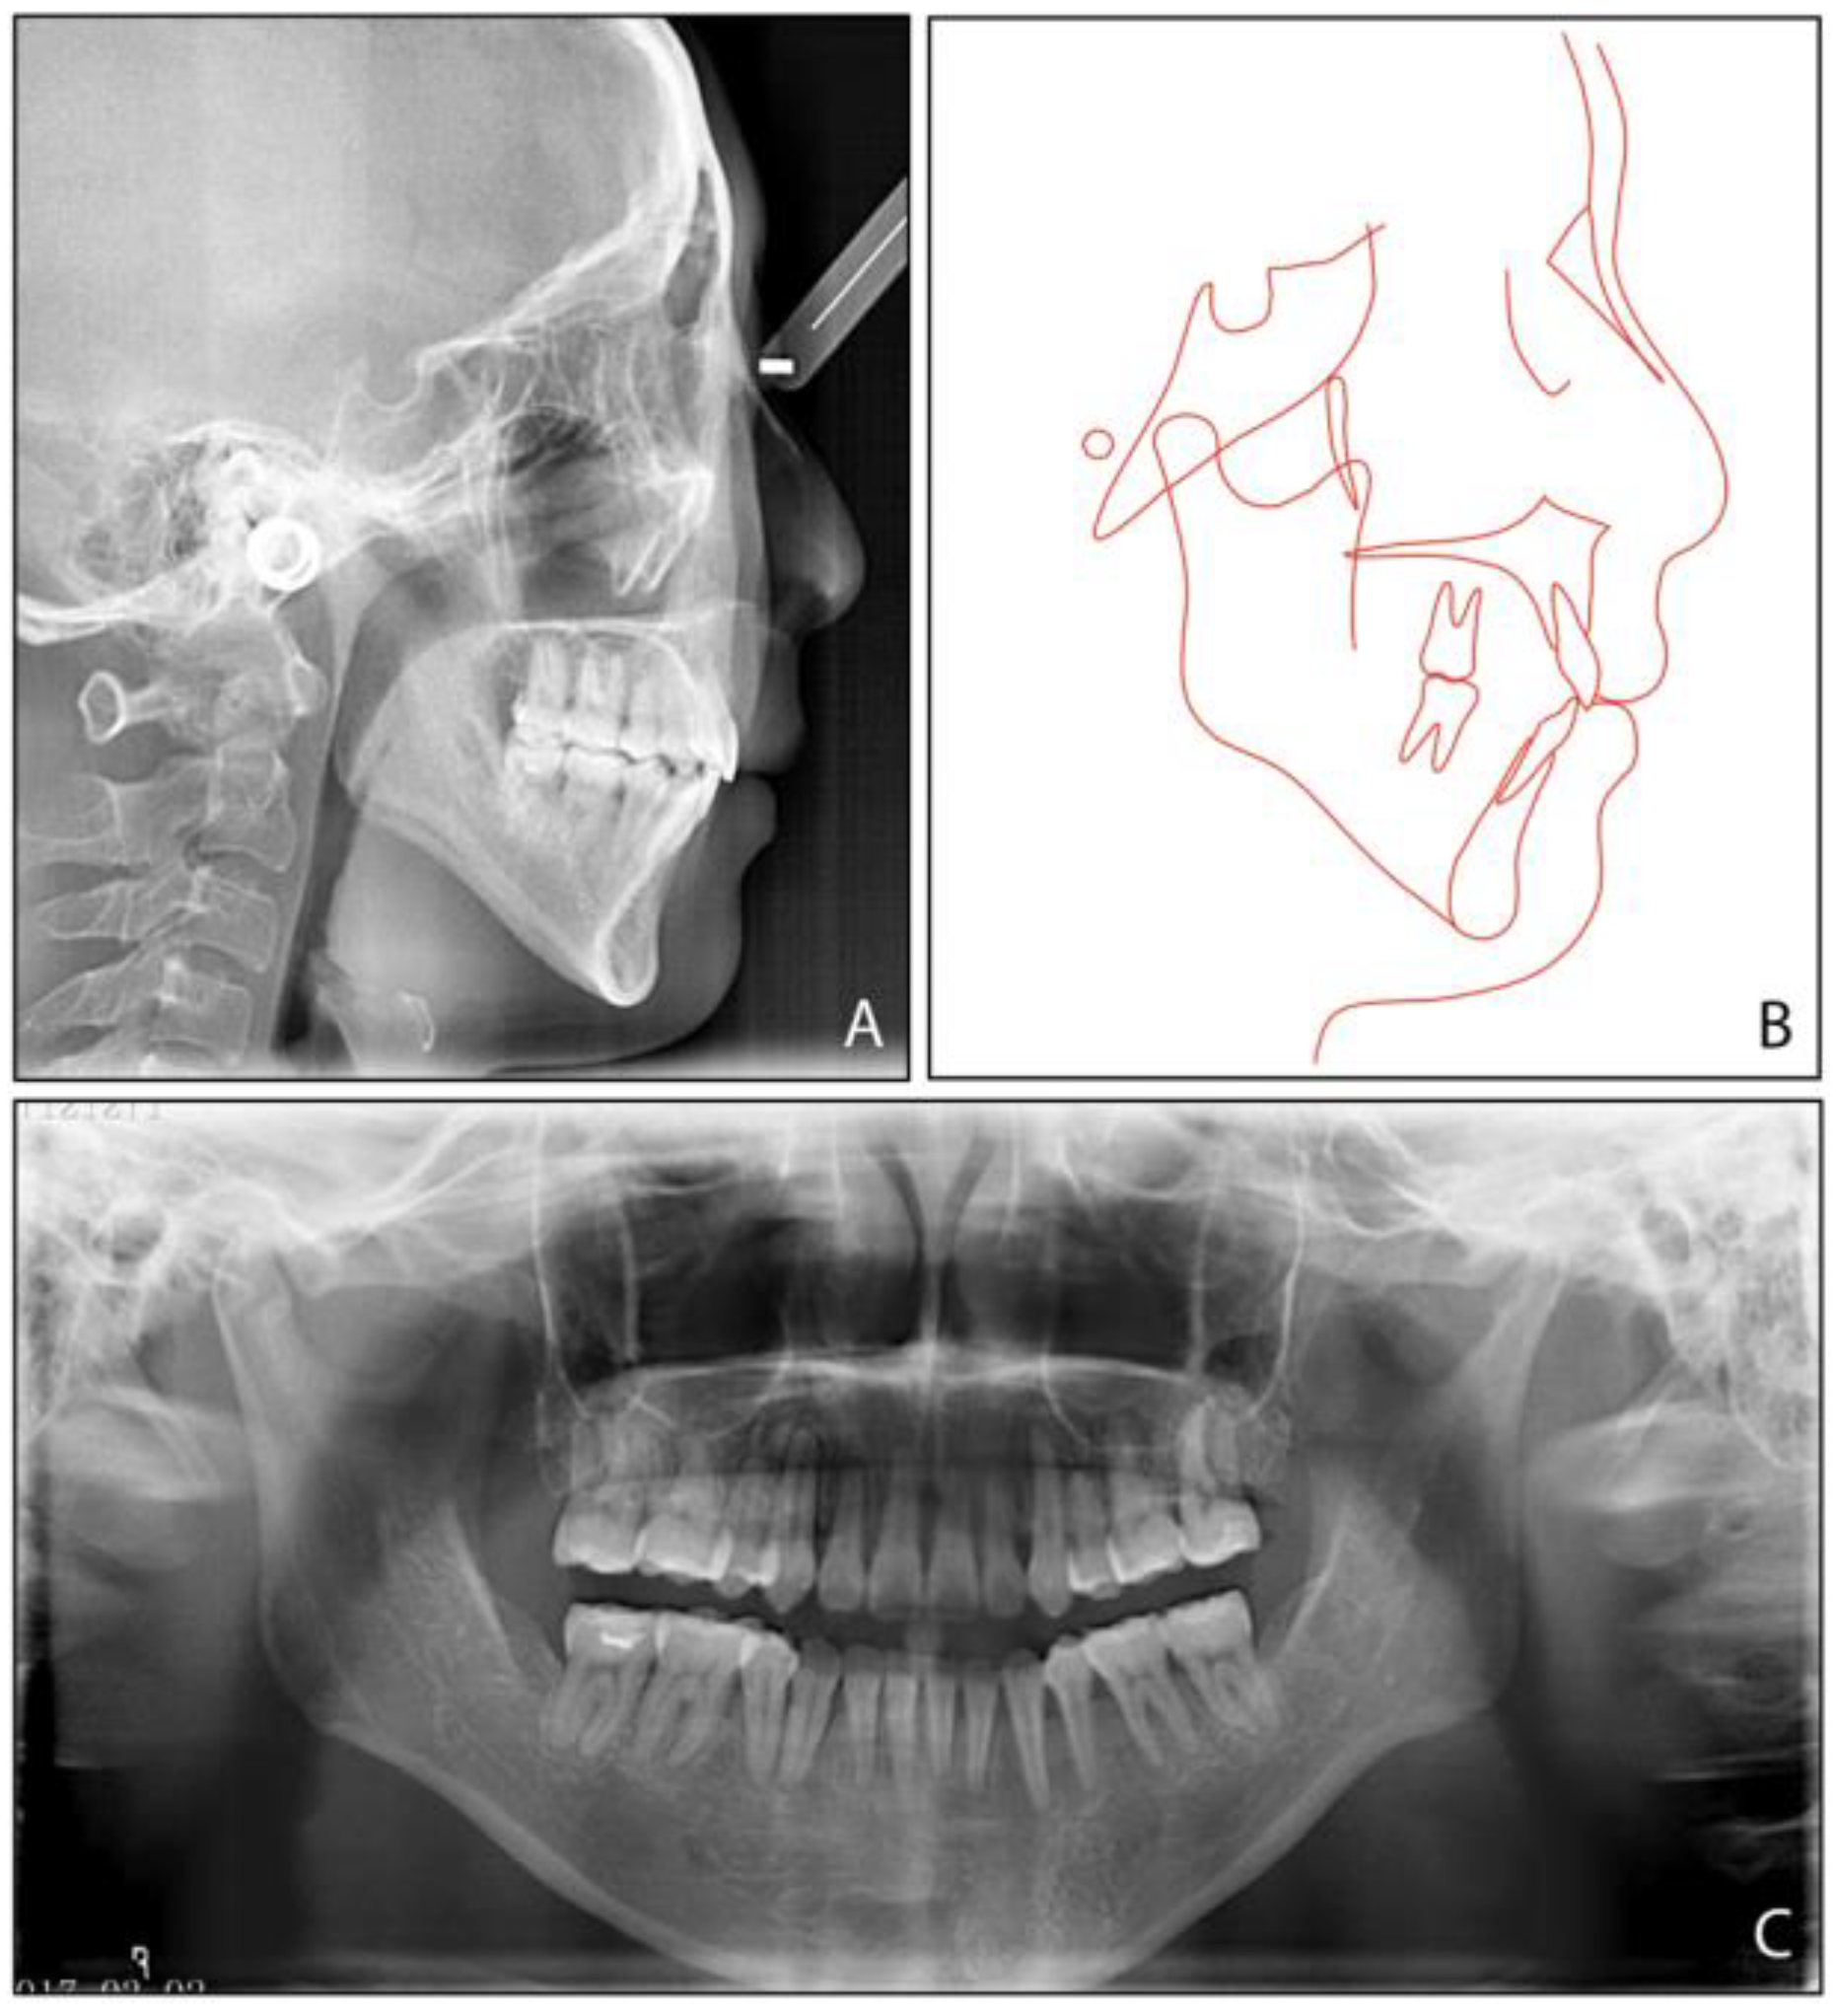

2. Case Report

2.1. Diagnosis and Etiology